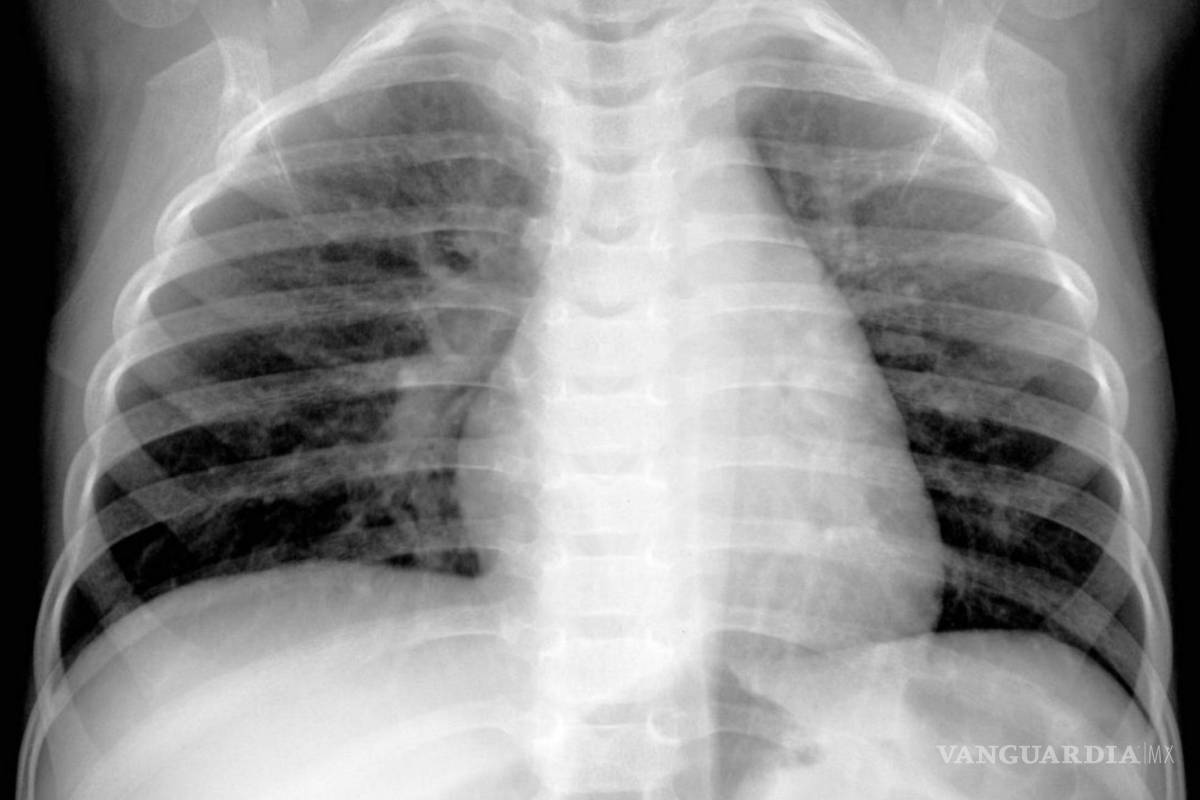

$!Una imagen de rayos X proporcionada por Hilmes et al., Pediatric Radiology, 2017 muestra a un niño de cuatro meses infectado por metapneumovirus humano.